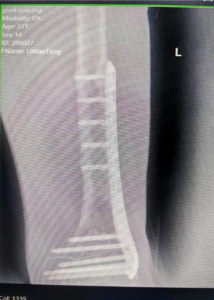

8月复诊时,患者左腿与右腿长度几乎持平

今年8月,当唐继全再次看到前来门诊复诊的李先生时,他的左腿已经与右腿长度几乎持平。随后,在唐继全的安排下,患者通过手术取出了内固定装置并进行检查。术后,李先生满心欢喜地表示,现在他终于能正常走路、跑步,日常活动不再受限了。

唐继全表示,Ilizarov外固定架可以使不愈合的骨头长在一起,使短缩的肢体延长,可以使久治不愈的骨髓炎愈合,从而让许多肢体残疾的患者恢复到受伤前的工作和生活中去。用克氏针经皮穿过骨头,外面连接一套外固定架,通过特殊装置调节外固定架就能达到矫正畸形、促进骨愈合、延长骨和肢体等作用。同时,唐继全提醒,实施Ilizarov骨延长手术后,患者需严格掌握康复程序和随访原则,避免、减少并发症的发生。